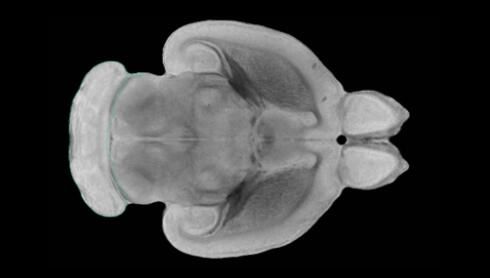

隨著機體年齡增加,肌肉和關節都會變得僵硬,這就會使得日常活動變得更加困難,本文研究表明,我們的大腦也是如此,與年齡相關的大腦僵硬對大腦干細胞的功能或許有著重要影響。文章中,研究人員對年輕和老化大鼠的大腦進行研究闡明了年齡相關大腦僵硬對少突膠質前體細胞(OPCs,oligodendrocyte progenitor cells)功能的影響。OPCs是一類對維持正常大腦功能非常重要的大腦干細胞,其對于髓磷脂的再生也非常重要,髓磷脂是神經組織周圍的脂肪鞘,在多發性硬化癥中髓磷脂的再生常常會被損傷,機體老化對這些細胞的影響常常會誘發多發性硬化癥的發生,這些細胞的功能在老化的健康人群中同樣會下降。

為了確定老化OPCs的功能缺失是否可以被逆轉,研究人員將來自老化大鼠機體的老化OPCs轉移到了年輕大鼠柔軟的海綿狀大腦組織中去,值得注意的是,這些老化的大腦細胞能夠重新恢復活力,其行為非常像年輕更加強壯的細胞。這項研究中,研究人員在實驗室中開發出了具有可變僵硬程度的新型材料,并在受控環境下研究這些材料的生長及其對大鼠大腦干細胞的影響,這些材料能被工程化改造具有和年齡或老化大腦相似的柔軟程度。

為了深入理解大腦組織柔軟和僵硬影響細胞行為的分子機制,研究人員對細胞表面一種名為Piezo1的蛋白質進行了分析,該蛋白質能“告知”細胞其周圍的環境為柔軟或僵硬。研究者Kevin Chalut說道,我們發現,當在僵硬材料上促進年輕具有功能性的大鼠干細胞時,這些細胞就會表現出功能異常,并失去其再生的能力,實際上其行為與老化細胞相似。當將老化的大腦細胞在柔軟材料上生長時,其功能就會表現得像年輕細胞一樣,換句話說,其能夠重新恢復年輕的活力。